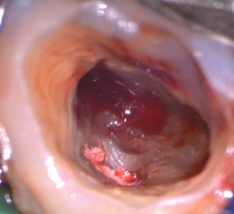

HFC(High Frequency Conduction:高周波通電)

高周波通電により、チップ電極の先端部と接触した部位を発熱させることで、組織の焼灼・凝固・切開を行うことができます。

根管長測定機能によって根管内のチップ電極の位置を設定し、フットスイッチを踏むことで1秒間のHFCが行えます。

2タイプのチップ電極を付属。どちらでも根管長測定、HFCが行えます。

チップ電極(ファイルタイプ) -

チップ電極(エンドファイルタイプ)

マイクロスコープ利用時の術野確保に有効です。